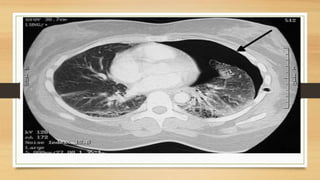

• Pneumothorax.

• Spontaneous pneumothorax.

• Traumatic pneumothorax.

• Iatrogenic pneumothorax, most commonly due to central line placement.

• Tension pneumothorax.